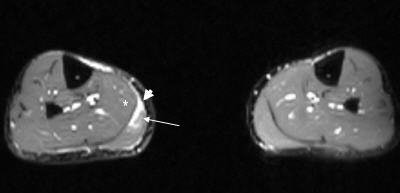

| Axial T2-weighted MR image of the legs shows increased signal in the medial portion of the right gastrocnemius muscle (white arrow) and fluid within the myofacial junction between the gastrocnemeius and the soleus (white asterisk) [Note: other leg is normal]. |

![]() |

| Axial T2-weighted MR image of the legs obtained just superior to image above demonstrates increased signal within the gastrocnemius (white arrow) indicative of the tear of the medial head of the muscle. |